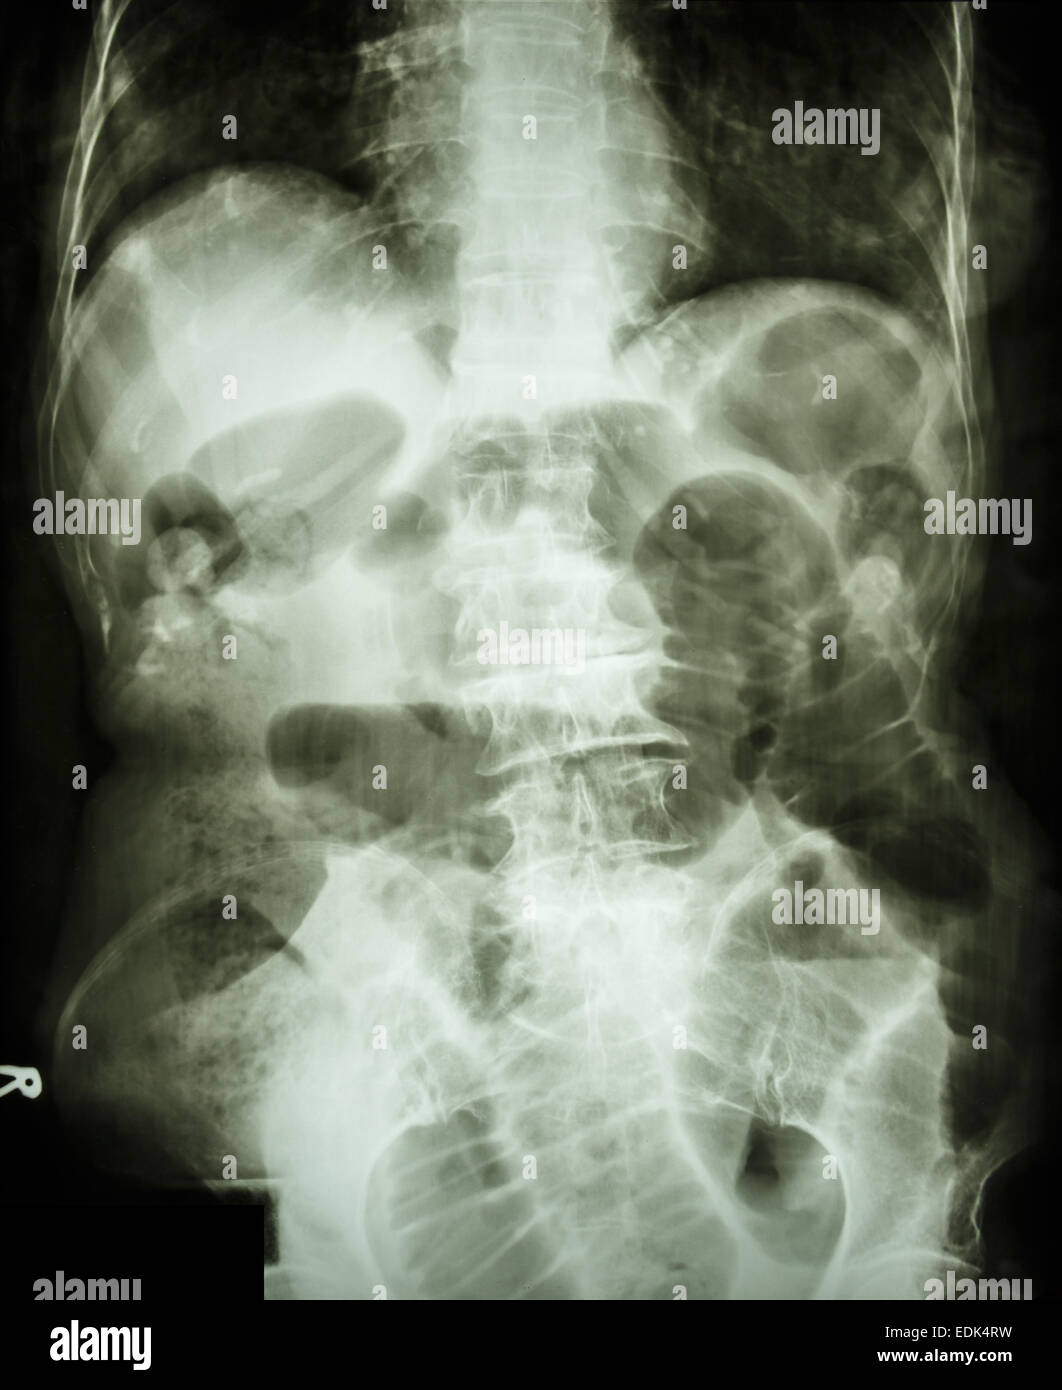

From www.alamy.com

"Small intestine obstruction" Film Xray abdomen supine Stock Photo Alamy Do X Rays Show Intestinal Blockage These images can also show air around your intestines or diaphragm (the. The main aims of imaging in cases of suspected bowel obstruction are: Surgery to remove the obstruction is often needed. Ct abdomen & pelvis with iv contrast: It can also be done to find an object that has been swallowed or to look for a blockage or a. Do X Rays Show Intestinal Blockage.